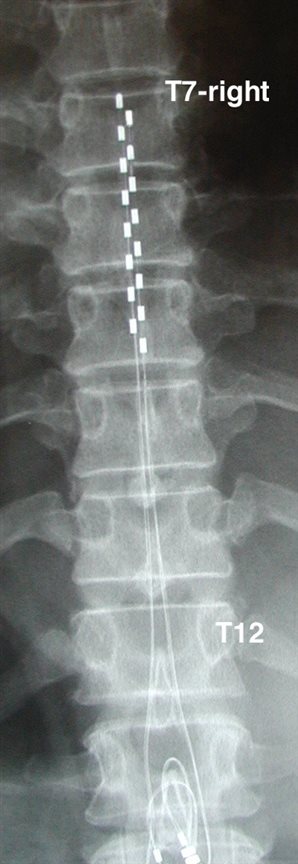

第一阶梯: 如果您的后遗神经痛对脉冲神经调控治疗反应良好,恭喜你,您中奖了,您的花费可能是数千元。手术在CT引导下进行,将电极定位到背根神经节,对受损神经进行调控: